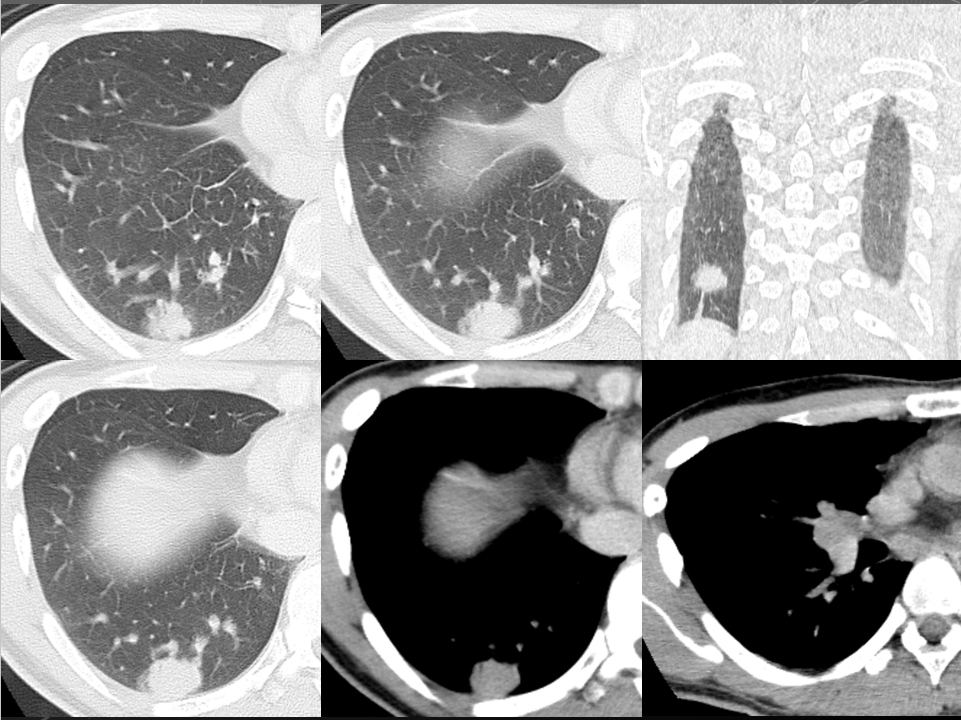

68F CEA 高値精査。消化器内科依頼。既往に脳梗塞、心筋梗塞、胃ポリープあり。

右肺下葉腺癌。

右肺下葉の縦隔側には最大径31mm大の不整形な腫瘤性病変を認めます。表面には部分的にspicula所見が見られ、胸膜に広汎に隣接するように存在しています。内部は辺縁を中心に淡い造影効果を呈しています。原発性肺癌病巣が疑われます。肺門部にはリンパ節腫大像が見られますが、縦隔領域に明らかに有意なリンパ節腫大は指摘出来ません。

左肺下葉に末梢側には淡い濃度上昇所見が見られ、GGO病変が疑われます。この他、肺野に明らかな腫瘤性病変は指摘できません。

右肺下葉原発性肺癌 ( adenocarcinoma )

右肺下葉原発性肺癌 ( adenocarcinoma )